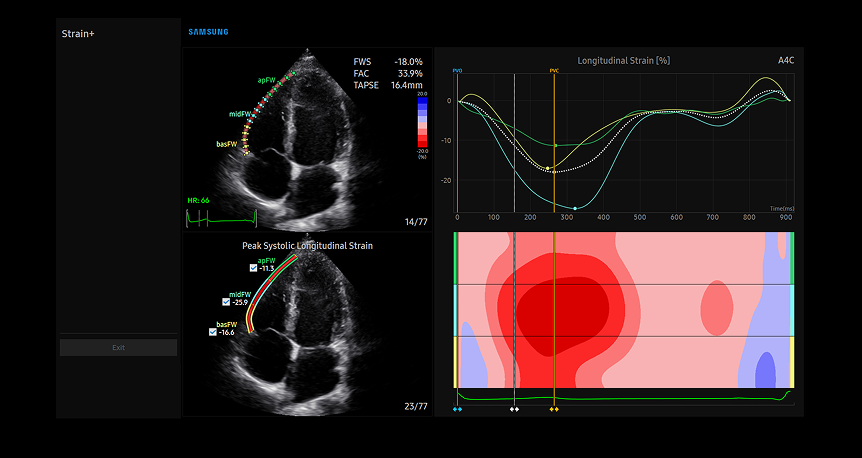

Strain+1 LV

Advanced Strain+ LV cardiac analysis on Samsung's diagnostic display showing multi-view heart chamber assessment with color-coded ventricular wall tracking and comprehensive bull's-eye plot visualization

Strain+ è uno strumento quantitativo per misurare il movimento della parete globale e segmentale del ventricolo sinistro (LV), dell'atrio sinistro (LA), di e del ventricolo destro (RV) per la funzione sistolica e diastolica del cuore.